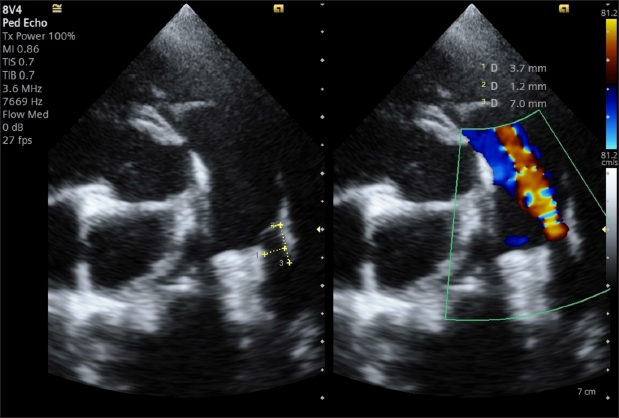

The stability of the device was subsequently tested with the push–pull “Minnesota wiggle” maneuver, and the cessation of transductal flow and the correct positioning of the device was verified using TEE (Figs. 4 and 5). The device was then deployed by rotating the delivery cable counterclockwise with the appropriate plastic vise. To verify the closure of the PDA and the absence of protrusions in the aorta further, a second angiography was performed as before (Fig. 6).

Fig. 6. Angiography conducted after device (arrow) release. The PDA is completely occluded and no residual shunt is visible.